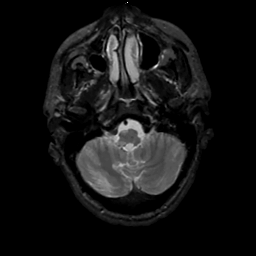

MR Study #1, February 10, 1991 -- Slice #8

[Home][Help][Clinical][Tour 1][Tour 2] Slice 8